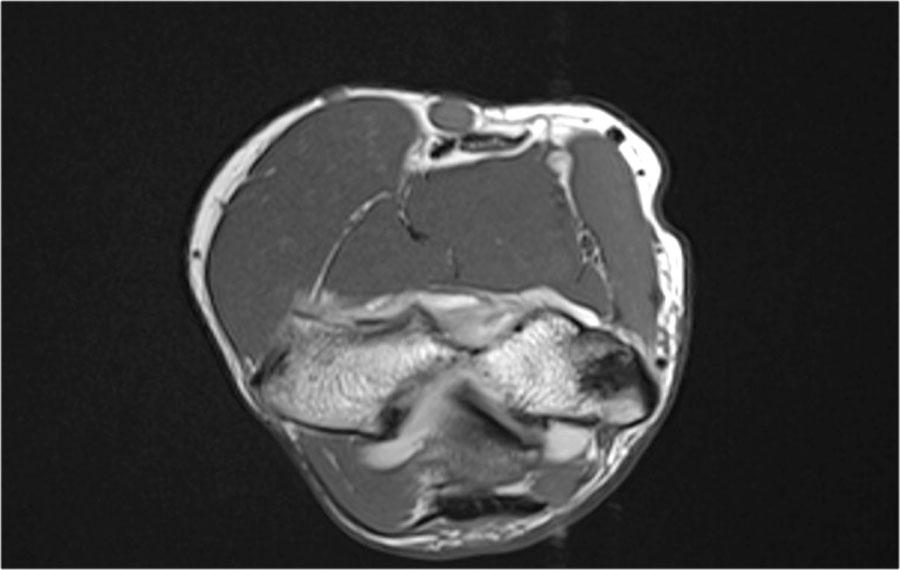

Notice also the fragmentation as seen on the axial image.